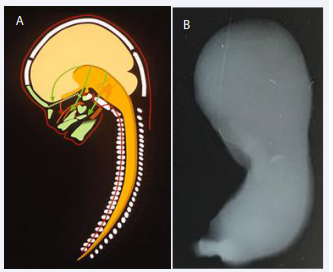

The cells forming the mandible have migrated from the neural crest as demonstrated schematically in Figure 2A. The Bony development of the claviculae are the first bones to ossify in the human body, shortly followed by ossification of the mandible [Figure 2B]. The bony formation starts in the canine region. Anterior to this region the mandible developed cartilaginously and posterior to that region the mandible developed membranously [Figure 3] [3].

Figure 2 A: Schematic drawing of the human body axis demonstrating the origin  of the vertebral column (illustrated by red marking of the notochord in the  corpora of the vertebrae) and the green craniofacial bones, originating from the  dark yellow neural tube. From the neural crest of the neural tube the multipotent  cells migrate anteriorly to form the craniofacial skeleton as demonstrated by  green arrows. Note that cells from different sites on the neural tube migrates to  different bony regions.  B: Illustration of a whole-body radiograph from a human fetus,7 weeks of  Gestation. The radiograph has been taken in a specific bone- sensitive X-ray  machine The right arrow indicates ossification of the clavicular bone, which is  the first bone in the human body to ossify. The left arrow marks the region in  which the mandible starts ossification, shortly after start of ossification in the  clavicula.